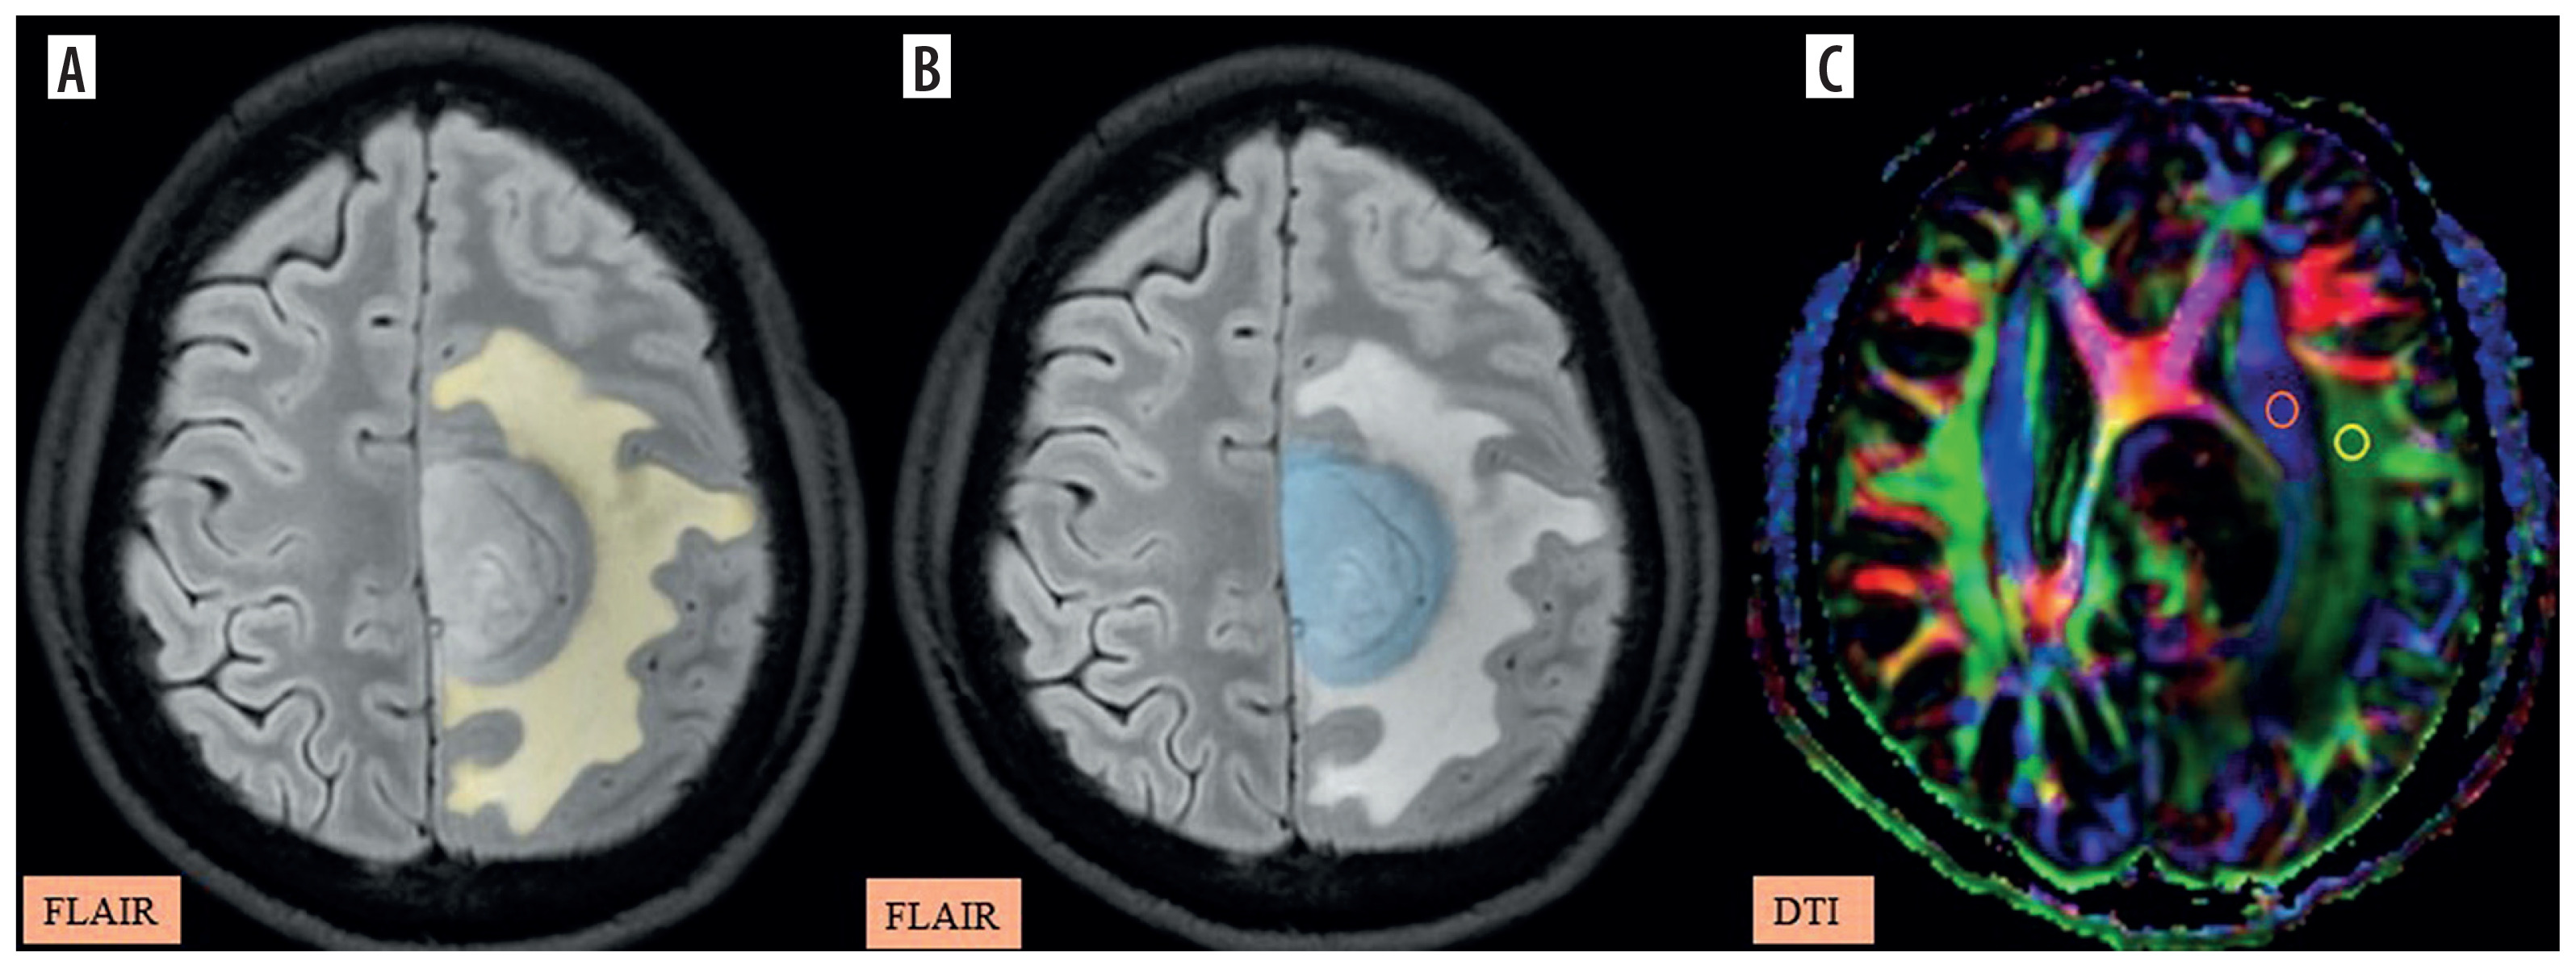

Figure 6

A-C) Patient with metastasis in the left frontal region presenting with right lower limb weakness and disorientation. A) Axial post-contrast T1 image shows the segmented tumour volume (blue). B) Axial fluid-attenuated inversion recovery (FLAIR) image shows the segmented peritumoral oedema (yellow). C) Image describing the calculation of the diffusion tensor image analysis along the perivascular space (DTI-ALPS) index using two regions of interest (ROIs) drawn within the projection (blue) and association (green) fibres in the left periventricular region